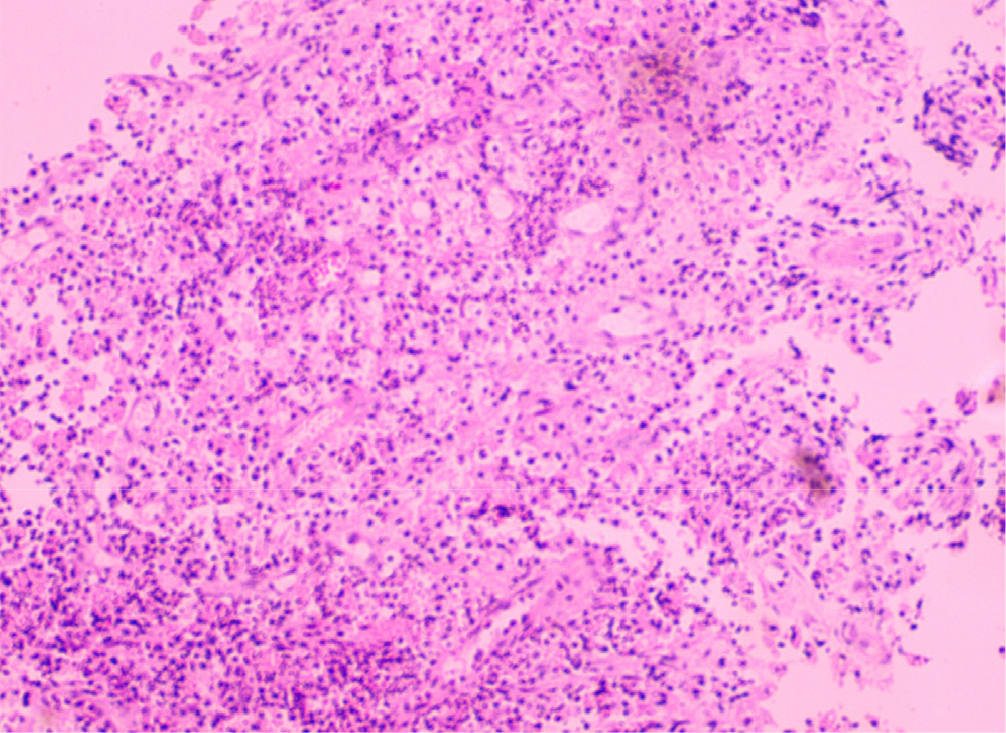

2.7. 병리검사

종괴는 황색종 세포와 만성 염증세포가 뒤섞여 있는 황색육아종성 방광염으로 확인되었다. 지질 함유 대식세포(lipid-laden macrophage)가 광범위하고 치밀하게 모여 있었고, 그 외에 육아 조직 (granulation tissue), 다핵 거대 세포 (multinucleated giant cell), 림프구의 집합(discrete collection of lymphocytes), 혈관 충혈(vascular engorgement) 및 약간의 출혈이 동반되었다. 간질에 분포하는 염증세포는 림프구, 혈장 세포, 호중구로 이루어져 있었다.